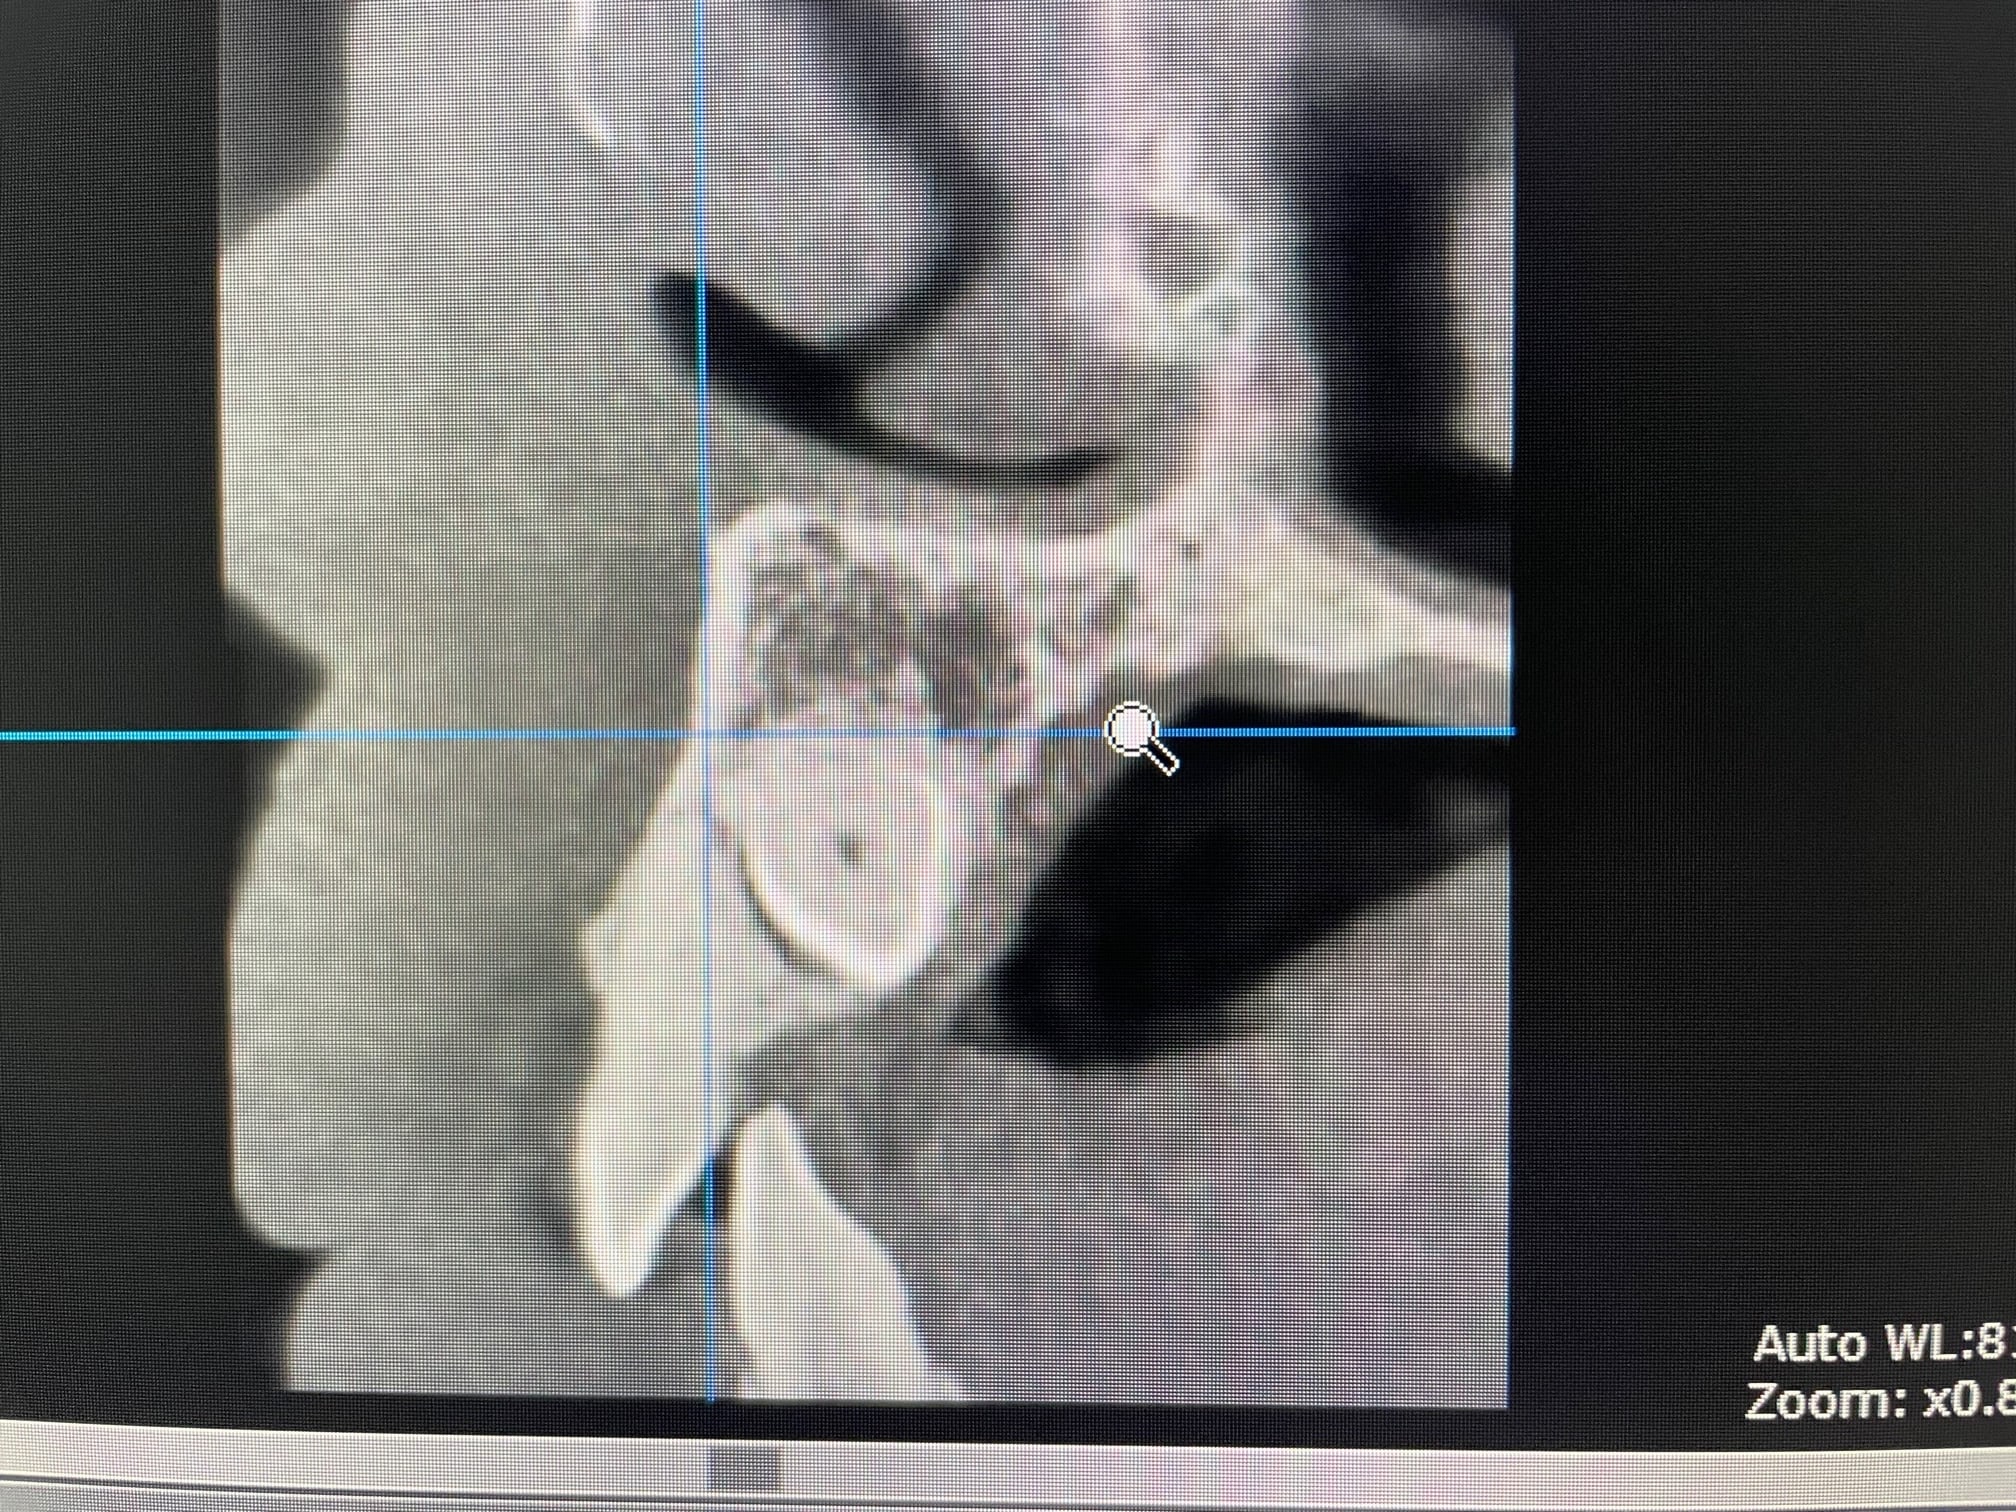

Dans le cas que tu as montré Gabzou le praticien a fait une effraction pulpaire…. Je te fais un petit zoom.

Dans ton cas Palpatine, je dis qu’il y a moyen de le faire sans effraction pulpaire. Foret initial et expansion (donc sans rogner d’avantage la dentine).

Moi je vois l'implant, 0.5 mm de zone forée vraiment sombre, puis 1mm de dentine moins dense, possiblement processus de résorption ou réactionnelle, puis zone vraiment sombre correspondant à l'endodonte. Cela dit, il peut y avoir eu une vraie perfo entre 2 plans de coupe de toute façon mais j'en doute, le patient ne rapportait pas de douleurs violentes suite à la pose de l'implant hors une contact direct aurait entrainé une pulpite. Il a pu oublier, mais en général on n'oublie pas une pulpite.

Après évidemment que selon la situation, on peut techniquement tenter de transfixer légèrement en évitant la pulpe, mais le risque de nécrose est toujours là de toute façon.

Tu vois ce que tu veux Gabzou :) hein …. Le mec est allé effleurer le nerf avec ses forêts. Faut pas s’étonner si derrière il y a eu des problèmes.

Ici l’axe de l’implant ne tombe absolument pas dans le nerf de la dent . Et il y aura une osteo intégration de l’implant sur le 1/3 sup , sur le 1/3 inf , et en vestibulaire quasi tout le long .